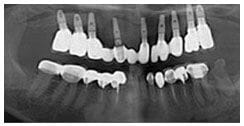

X 光片

術前X光片

術後X光片